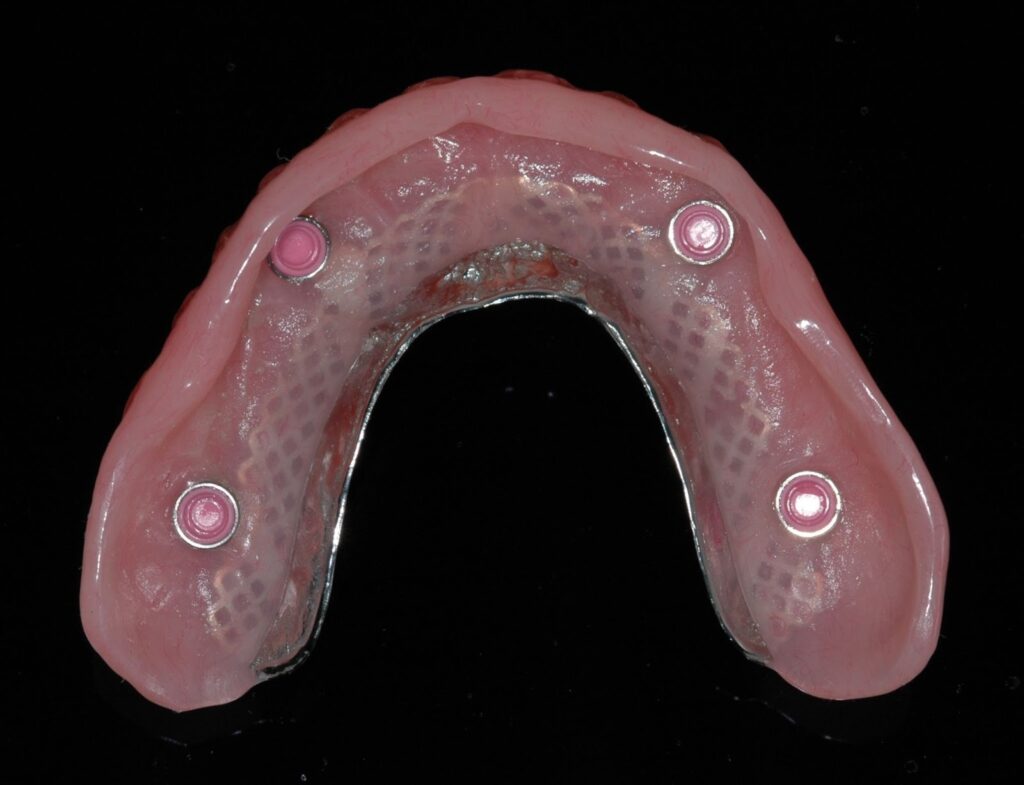

3. Implant-Retained Dentures

These dentures look similar to traditional removable dentures but are less bulky and snap onto dental implants for stability.

Best for: Patients who struggle with loose dentures.

Comfort level: Excellent – dramatically more stable than traditional dentures.

Material: Metal framework is hidden for strength and wrapped with acrylic.

Adhesive use: Not needed

As few as two implants in the lower jaw and four in the upper jaw can significantly improve comfort and chewing efficiency.